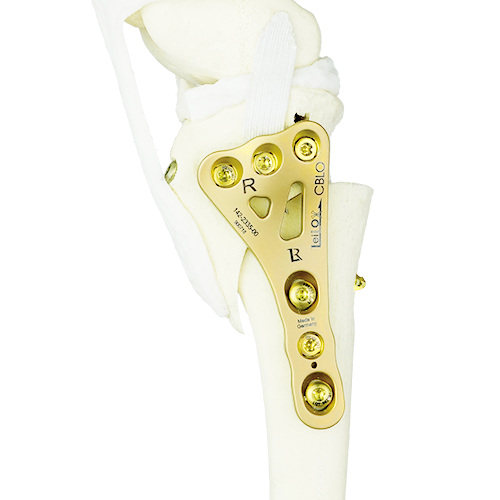

Products

Technology Leading Manufacturing

A Titanium LeiLOX CBLO Plate is born in one of our in-house machines: